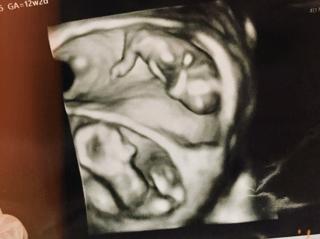

写真:12w2d:スパロウさん

胎児ドッグでの初4Dエコーです!異常もなく、心配ごともなくなり、これで産まれてくるのを待つのみです♪終始動き回ってるので、ブレブレ写真になりましたが、しっかり成長してます!

前回まではよくわからない可愛いい生き物のような形でしたが、しっかり人間の形になっていたことに感動!

なんとなくパパ似で、男の子かな?と思いました。